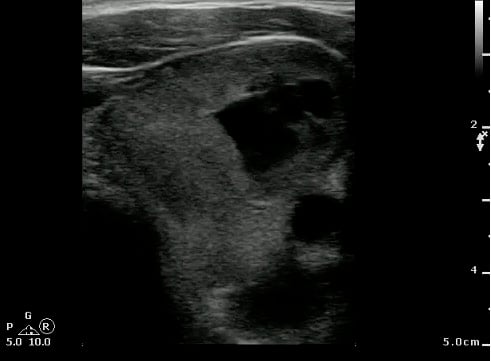

Thyroglossal duct cyst26

- Thyroglossal duct cysts typically related to hyoid bone:

- Often midline

- 25%-suprahyoid-submental region

- 75%-Infrahyoid or at the level of hyoid

- Variable sonographic appearance:

- Well-circumscribed anechoic cyst

- Increased through transmission

- Hypoechoic with internal debris

- No internal vascularity

- Heterogeneous pattern seen in repeated infections and hemorrhage due to prior aspirations

- Pseudo-solid echogenic appearance from proteinaceous contents secreted by epithelial lining

- Figure 34 and 35. Thyroglossal Duct Cyst

Video 22. Thyroglossal Duct Cyst